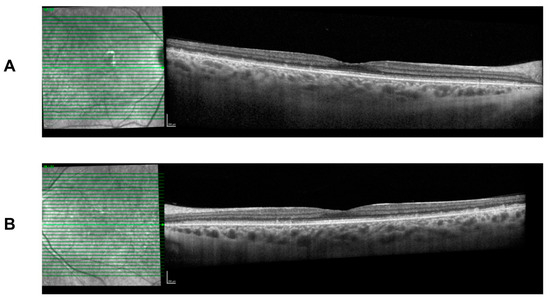

She continues to present with the typical FAP phenotype of small subretinal white dots 360 degrees throughout the fundus, particularly in the mid-periphery with fundoscopy and retinal imaging (Figure 4). The white dots spare the fovea region and preserve her visual acuity. Spectral-domain optical coherence tomography (SD-OCT) imaging is stable over time and shows the presence of subretinal deposits, attenuated ellipsoid zones, and a thick choroid in both eyes (Figure 5).

Figure 5.

Spectral-domain optical coherence tomography (SD-OCT) at age 26 with deep retinal deposits that are fovea sparing. There is mild attenuation of the ellipsoid zone and a thick choroid. Findings are symmetrical in both eyes. (A) Right eye. (B) Left eye.

Throughout follow-up assessments and imaging, the natural history and progression of the patient’s FAP has shown a stable clinical phenotype. Nyctalopia and light vision deficits have subjectively remained stable with delayed dark adaptation. The patient’s best-corrected visual acuity continues to remain stable over 7 years; however, the patient’s color vision assessments indicate there may have been a progression of color vision deficits between the ages of 5 and 21. OCT imaging has remained stable over time, showing a lack of fovea involvement and little impact on central vision.